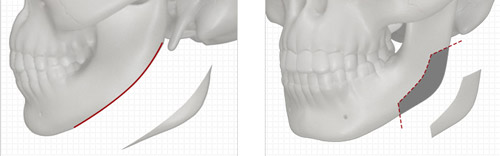

“脸大毁所有”这话真不是瞎扯!每次自拍都得找角度,合照永远躲在后排,连扎个马尾都要被调侃“国字脸显凶”——这些苦,只有下颌角宽大的姐妹才懂。不过别慌,今天要聊的这位“改脸型大神”张笑天,专治各种“脸型不服”,从三维模拟到术后结果,全程给你安排得明明白白!

2025-06-22 00:15:01 九粥